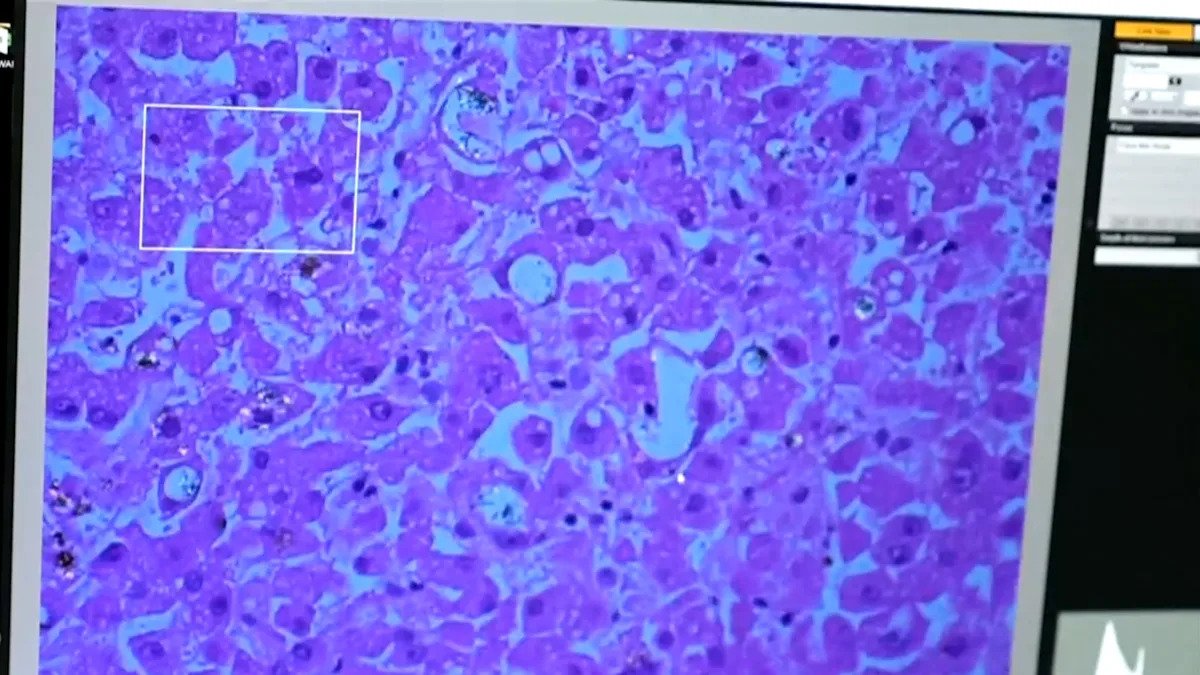

Albuquerque, New Mexico — Dr. Matt Campen studies the health effects of environmental pollutants. His lab at the University of New Mexico has, for the first time, found plastics in human brain tissue.

Campen’s lab has found more plastic in the brains of people with dementia than those without dementia.